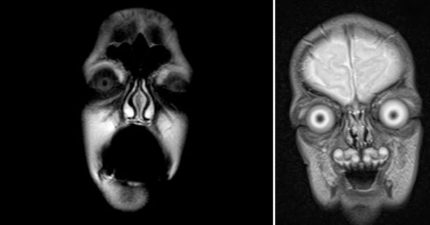

當你在做MRI核磁共振的時候,一個很可怕的事情會發生。